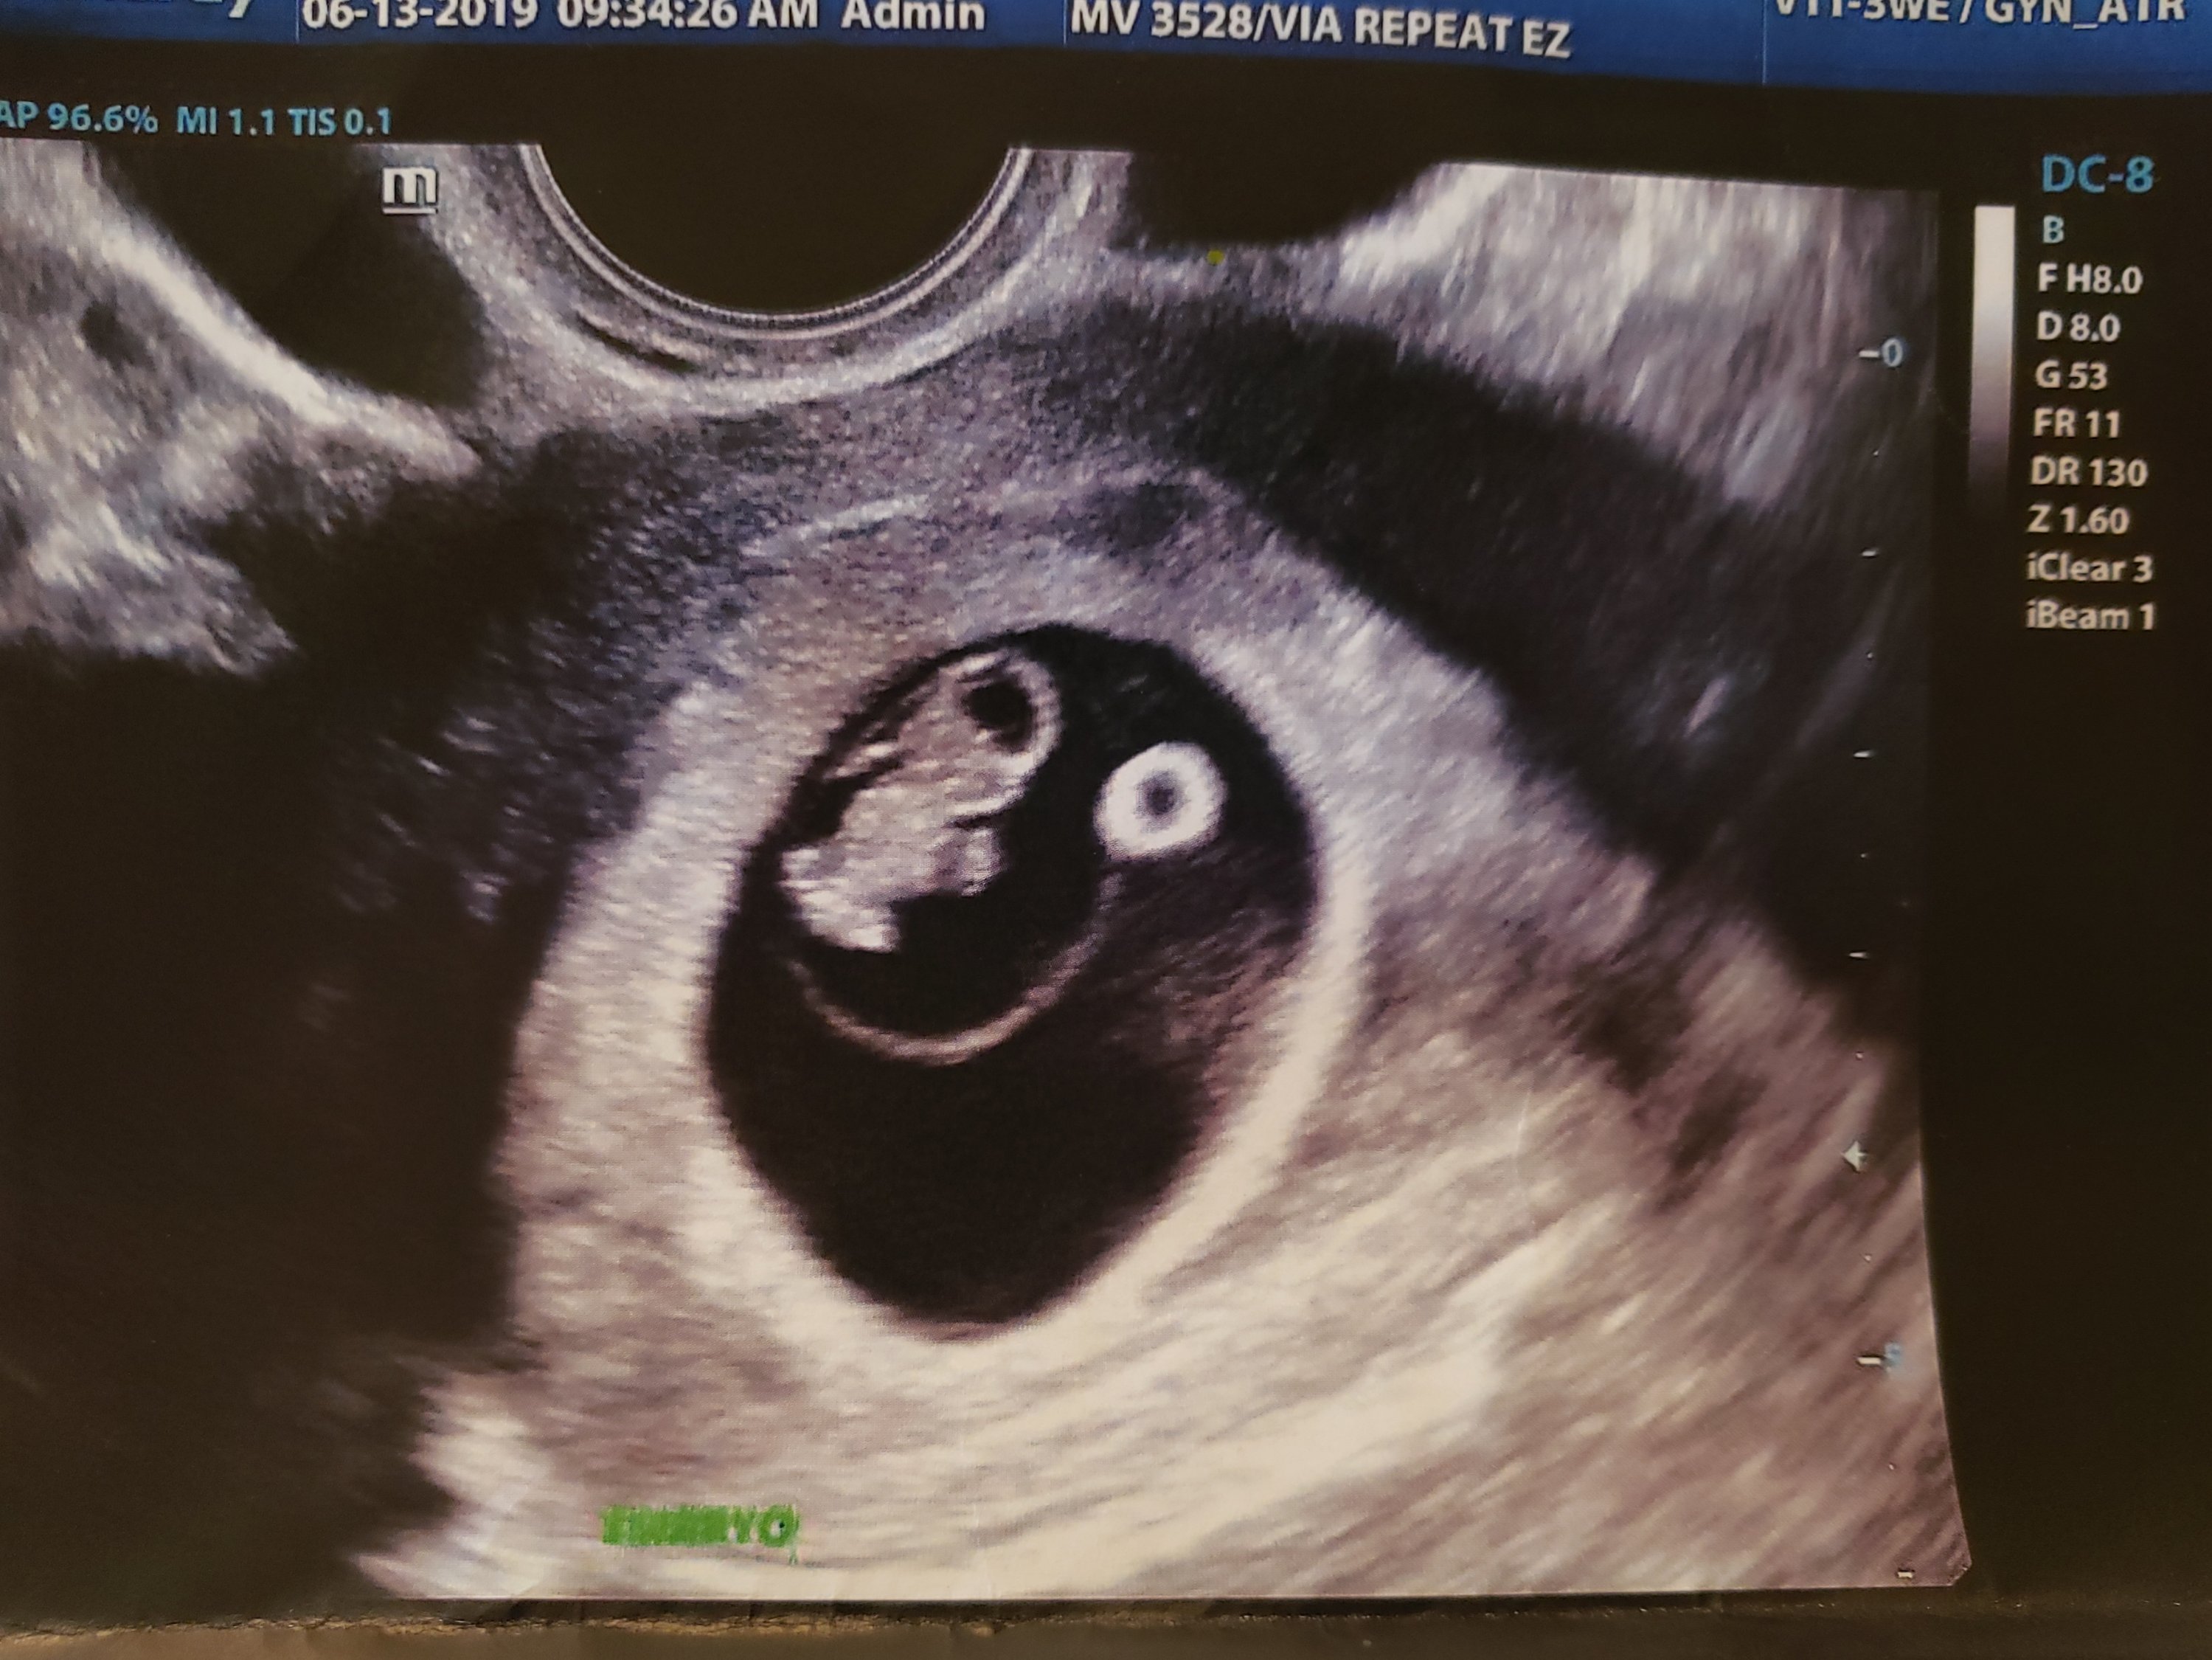

I had another ultrasound yesterday, at my 8 week mark.

Due date confirmed: January 25, 2020.

Looks a little more human now; see ya, Sigourney!

Note the head, 2 little arms starting, and the very beginning of legs.

Okay, maybe more like a gummi bear… which, fittingly, is about the size of it now. Or, if you prefer, a raspberry. It’s more than doubled in size in a week, now measuring 1.5 cm long, and weighing in at .04 ounces. Baby grows about a millimeter each day.

Beside the wee gummi is the yolk sac that has been providing all the nourishment, but it is rapidly shrinking as the placenta continues to develop, gearing up to take over that important task by 12 weeks.

At this stage, eyes are moving towards the middle of the face, and nerve cells in the eyes are beginning to develop. The little bean grows longer this week, marking the end of the embryonic period. Soon it will begin to straighten out. Notice the tail is already gone? Yay!

The heart rate was 163 bpm, which is exactly within the desired range, so all is well there.